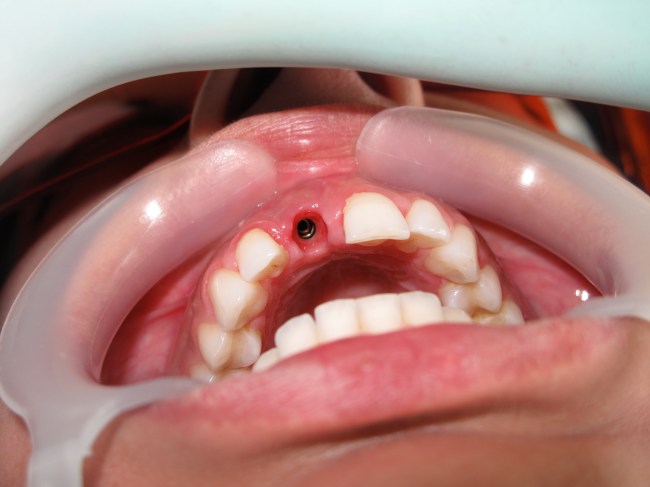

Dental implants are most difficult in the esthetic zone especially when it needs Bone graft management.